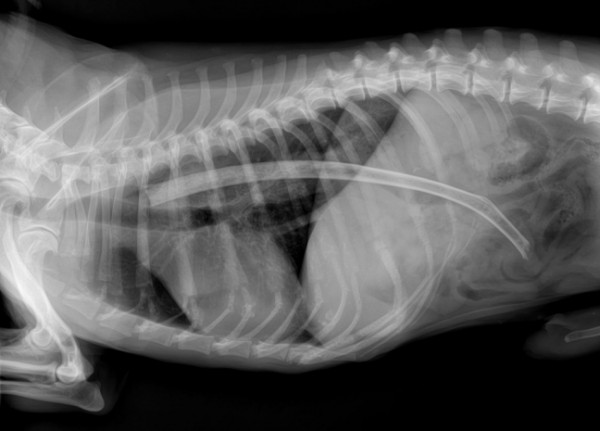

وأظهرت تلك الصور واللقطات صوراً بالأشعة السينية لبطون الحيوانات، أبرزها ابتلاع جرو صغير سكيناً طولها 120 سنتيمتراً؛ ما يوازي نحو 30 بوصة.

وأظهرت تلك الصور، التي التُقطت من قِبل مجموعة من الأطباء البيطريين، كيف أن الحيوانات تبتلع أحيانا أشياءً غريبة، مثل ابتلاع كلب آخر ضلع كامل لحيوان، فيما ابتلعت قطة أذرع تحكم "بلاي ستيشن".